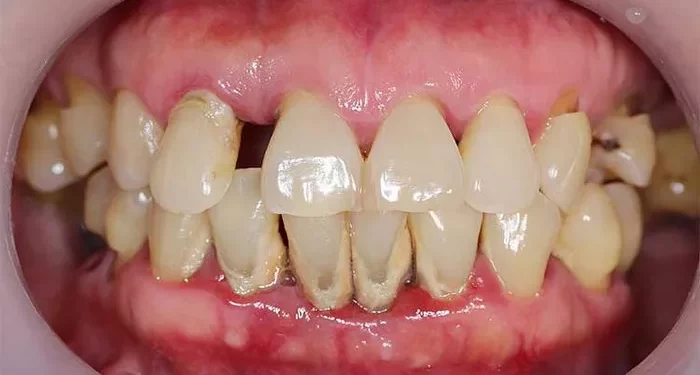

Periodontal disease often begins with dysbiosis in the oral microbiome, where harmful bacteria outgrow beneficial ones, leading to inflammation and damage to the surrounding tissues. Excessive sugar intake encourages the growth of pathogenic bacteria and contributes to the formation of biofilm—a sticky bacterial layer on teeth that drives inflammation in the gums. Over time, this can result in periodontitis, a more severe form of gum disease marked by deep pockets around the teeth, bone loss, and loosening of teeth.

The effects of periodontal disease extend far beyond the mouth, as it is linked to several systemic conditions, including cardiovascular disease, inflammatory bowel disease, and neurodegenerative disorders. The connection between oral health and these conditions is bidirectional, as each can exacerbate the other through shared inflammatory pathways.

In the mouth, excessive sugar consumption similarly reduces microbial diversity, promoting the growth of disease-causing bacteria such as Streptococcus and Actinomyces, which are commonly involved in periodontal disease. Even short-term exposure, such as rinsing with sucrose, can disturb the microbial balance and accelerate the development of harmful bacteria, ultimately leading to gum inflammation and periodontitis.